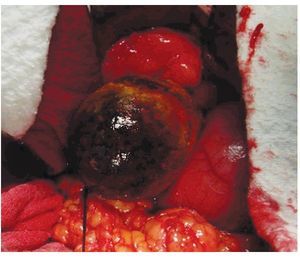

Se trata de paciente femenino de 75 años de edad, la cual acude al servicio de urgencias por presencia de vómitos en varias ocasiones de contenido gástrico, intolerancia a los alimentos, malestar generalizado y datos francos de deshidratación secundaria, con 15 días de evolución desde el inicio de su padecimiento. La paciente tiene antecedentes de diabetes mellitus, hipertensión arterial y refiere gastritis crónica en tratamiento. A su ingreso se encuentra orientada, conciente y sin datos de alarma abdominal, por lo que es internada para su estudio y estabilización con sospecha de cuadro de estenosis péptica pilórica. Se coloca sonda nasogástrica drenando aproximadamente 3 L de material gástrico espeso y restos de alimentos. Laboratorios a su ingreso con hemoglobina de 10 mg/dL, leucocitosis de 13,000 mm3, glucosa 96 mg/dL, urea 30 mg/dL, creatinina 1.8 mg/ dL. Una vez con la paciente en mejores condiciones, se decide realizar panendoscopia encontrando un cálculo biliar gigante impactado en el bulbo duodenal (Imágenes 1 y 2) realizándose múltiples maniobras de extracción con pinzas de cuerpo extraño, las cuales no fueron exitosas. Se realizó ultrasonido demostrando la presencia del cálculo impactado en duodeno, no se apreció dilatación de vías biliares (Imagen 3). Con estos hallazgos se decide someter a la paciente a cirugía, encontrando la presencia de un cálculo biliar gigante dentro del bulbo duodenal con vesícula biliar escleroatrófica, se realiza duodenotomía y extracción del cálculo con duodenorrafia en 2 planos tipo Heineken-Mikulicz sin incidentes transoperatorios (Imágenes 4, 5 y 6) y con adecuada evolución, siendo egresada al octavo día del posoperatorio.

Imagen 2. Cálculo biliar impactado en duodeno.

Imagen 4. Duodenotomía y extracción del cálculo biliar.